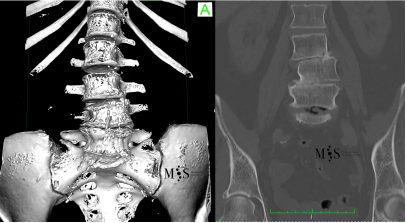

Figure of a degenerative scoliosis. OPlease note the deviation and asymmetry

of the lumbar verebrae and the black disk at L5/S1 (sign of instability).